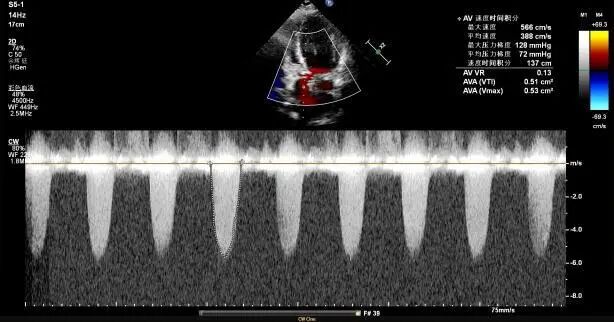

高龄患者,因“反复胸痛2年,加重伴气促1周”入院,超声心动图提示主动脉瓣极重度狭窄(图A),主动脉CT提示三叶式主动脉瓣,瓣叶增厚,重度钙化,L-R钙化高位粘连(图B),患者已有心源性休克、晕厥的表现,病情危重,更为棘手的是,患者同时存在反复消化道出血,经多学科会诊,明确诊断为海德综合征(Heyde综合征)——一种因主动脉瓣狭窄导致胃肠道血管发育不良继而引发出血的严重并发症。

A:超声心动图:频谱多普勒提示主动脉瓣前向流速 5.66m/s;主动脉瓣功能性二叶瓣畸形(左右冠瓣融合型,Type1型)瓣叶明显增厚、钙化伴主动脉瓣狭窄(重度+)